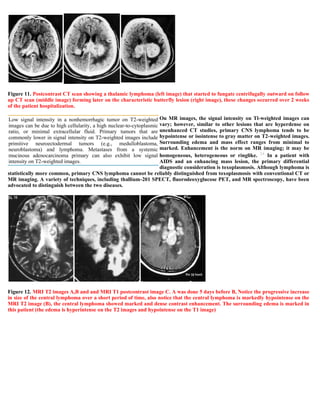

A 32-year-old male presented with a single grand mal seizure. CT scans showed extradural masses in the left parietal and frontal regions, compressing the brain and ventricles. Surgery revealed nodular dural thickening without brain infiltration. Biopsy diagnosed non-Hodgkin B-cell lymphoma. Further staging found extensive extraneural disease, though the CNS manifestations were the initial presentation. The patient was referred for oncology management for epidural secondary CNS lymphoma.